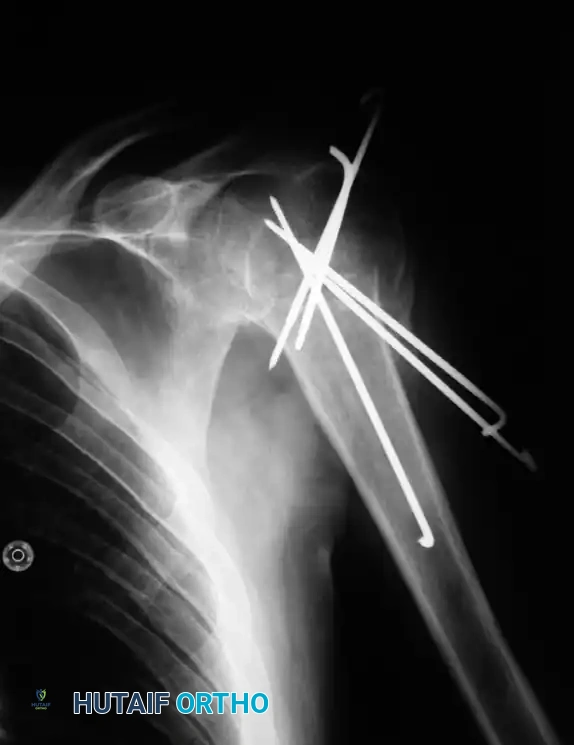

التثبيت بالدبابيس عبر الجلد

تُعد هذه الطريقة خياراً فعالاً للكسور التي يمكن إعادتها لمكانها الصحيح دون الحاجة لفتح جراحي كبير. يتم إدخال دبابيس معدنية خاصة عبر الجلد لتثبيت العظام تحت توجيه الأشعة السينية المستمرة داخل غرفة العمليات.

من شروط نجاح هذه العملية أن تكون كثافة العظام جيدة وألا يكون الكسر مفتفتاً بشدة. ورغم أن هذه الطريقة تحافظ على الأنسجة المحيطة، إلا أنها تتطلب دقة متناهية من الجراح لتجنب إصابة العصب الإبطي الذي يمر بالقرب من منطقة إدخال الدبابيس.

إليك بعض الصور الإشعاعية والرسوم التوضيحية الإضافية التي توضح أشكال التثبيت الجراحي المختلفة لكسور أعلى عظمة العضد